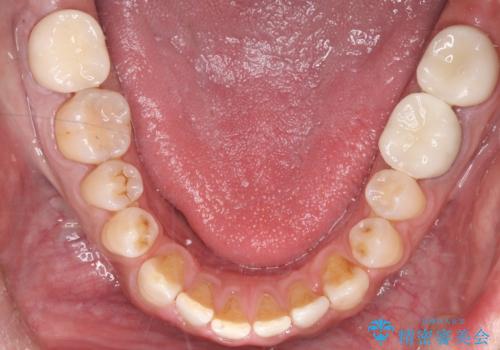

オールセラミックによる修復: 天然歯のような光の透過性と硬さを持つオールセラミックを使用しました。奥歯であっても、患者様固有の歯の色調や咬み合わせの溝を忠実に再現した修復物を装着。金属を一切使用しないことで、金属アレルギーのリスクを排除し、歯肉の色が黒ずむ心配もなくなりました。

【治療の結果】 全ての銀歯が白くなったことで、お口の中がパッと明るくなりました。見た目の美しさだけでなく、表面が滑らかなセラミックはプラークが付着しにくいため、将来的な虫歯や歯周病の予防効果も高まった健康的な口腔環境が実現しました。